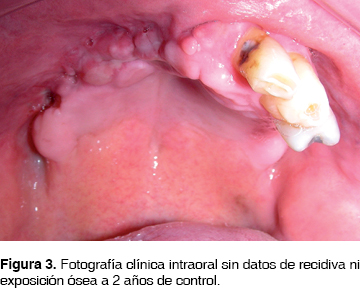

Se envía la pieza quirúrgica a patólogo oral reportando osteomielitis crónica maxilar con bordes libres de lesión. Continúa tratamiento antimicrobiano ambulatorio con penicilina G procaínica 800,000 UI IM cada 24 h por 30 días. Posteriormente se envía al servicio de prótesis maxilofacial para su rehabilitación, actualmente continúa asintomático a 2 años de control y sin datos de recidiva (Figura 3).